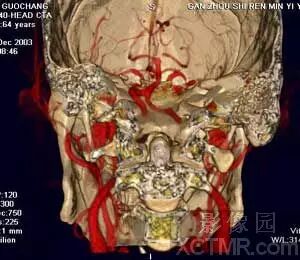

VR作为MS-CTA的主要后处理技术在血管系统特别是对动脉血管系统病变要以清晰、确切地显示大范围复杂血管的完整形态、走行和病变,图像立体感强,能以多角度直观地显示病变与血管、血管之间以及血管与周围其它器官之间的三维空间解剖关系,其诊断价值已经被临床医生认可。对大动脉血管病变如:动脉瘤、动静脉畸形、狭窄、梗塞、闭塞、夹层和血管壁的钙化等的诊断已经基本取代了DSA检查。对脑动脉瘤的诊断国、内外有关研究报告证实3D-CTA具有很高的准确性、敏感性和特异性,可以确切地检出瘤体直径<3mm的脑动脉瘤。作为一种快速和非创伤性检查手段,可以准确地显示瘤体的位置、形态和大小,评价瘤颈部与瘤体、载瘤动脉和周围血管之间的空间关系,模拟手术入路为选择适当的手术治疗方案提供直观、可靠的依据,可以作为脑动脉瘤的首选影像学诊断方法。近年来,有许多文献报道主张用3D-CTA取代或部分取代DSA诊断脑动脉瘤。

脑动脉CTA数据采集要求:

a)采集层厚≤ 3.0mm/每层;

b)重叠重建间隔≤ 2.0mm;

c)选用软组织重建函数,如FC=10/43;

d)对比剂用量1.0-2.0ml/kg;

e)注射速率2.5-3.0ml/sec;

f)延迟时间15-20sec.,必要时可用对比剂跟踪技术(Sure-Start);

g)扫描方向自下而上;

h)对Willis环动脉瘤扫描范围自第一颈椎向上10cm,并尽量采用放大扫描技术。